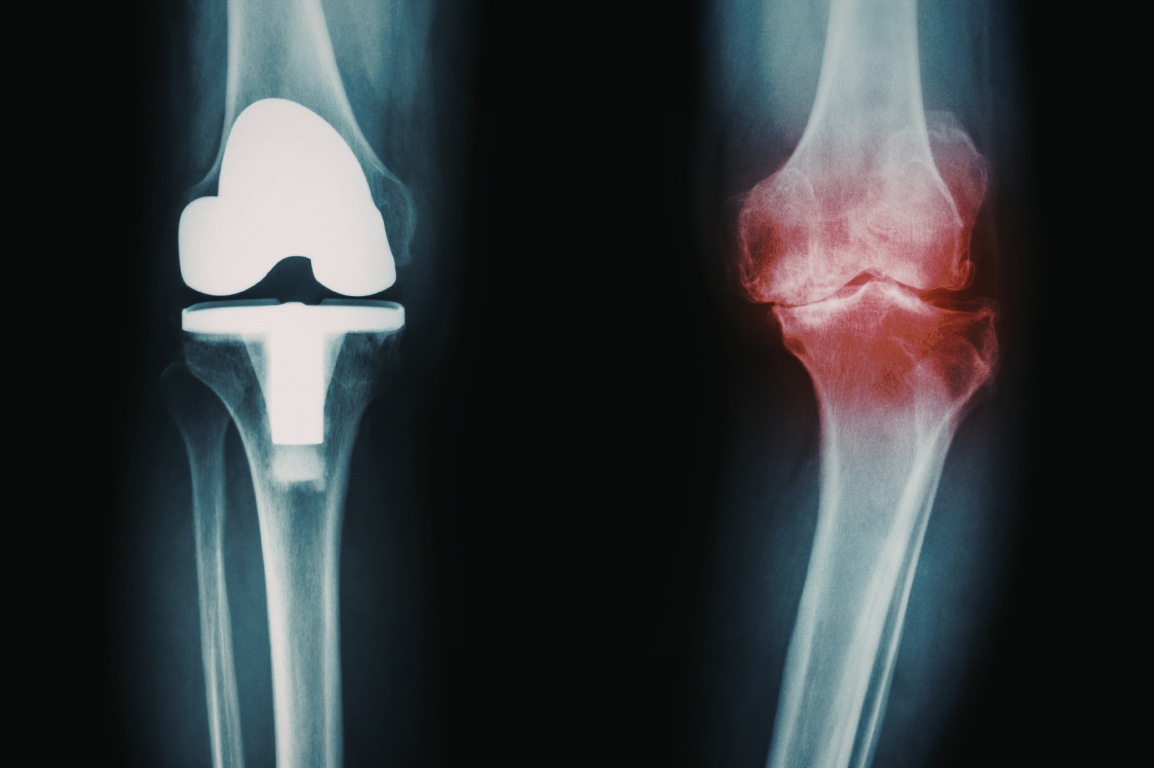

Understanding Knee Conditions

Knee conditions can develop from injury, wear over time, or repetitive stress.

The knee is a complex, weight-bearing joint that’s constantly in use, making it especially vulnerable to strain, instability, and gradual degeneration.

Some issues develop suddenly from injury, while others build over time due to cartilage wear, inflammation, or movement imbalances.

Although symptoms like pain, stiffness, or instability may feel similar, the underlying cause can vary—from ligament injuries and cartilage damage to overuse or joint degeneration.

Understanding the source of the problem is key to choosing the right path forward and preventing long-term limitations.

Injury-related conditions such as meniscus tears, ligament injuries (ACL, MCL, PCL, LCL), tendon tears, or patellar instability can affect movement and joint stability. Degenerative conditions like osteoarthritis, post-traumatic arthritis, or inflammatory joint conditions may develop over time and lead to stiffness, swelling, or reduced mobility.